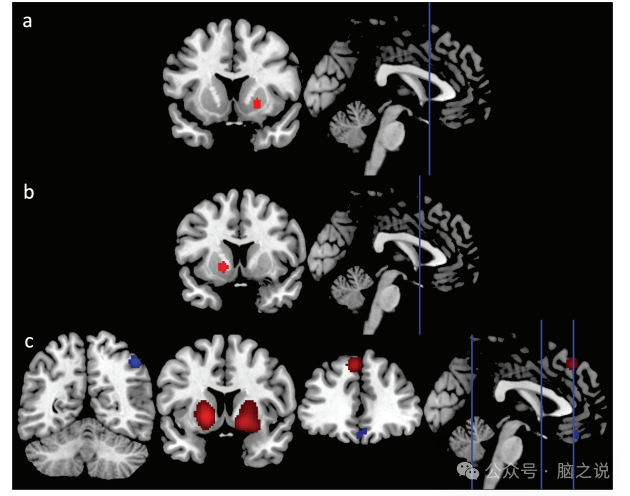

AIFF / fAIFF。与HC相比,FEP在右侧纹状体具有更高的AIFF/fAIFF[峰坐标(x,y,z) = 22,12, - 6]。

ReHo。与对照组相比,我们观察到左侧纹状体FEP的ReHo显著增加[峰坐标(x,y,z) = - 16,10, - 4]。

所有的测量。与对照组相比,FEP组的AIFF/fAIFF和ReHo值在右侧纹状体[峰坐标(x,y,z) = 18,14,−2]、左侧纹状体[峰坐标(x,y,z) =−18,12,−2]和左侧SFG/MFG[峰坐标(x,y,z) =−4,36,46]显著增加。此外,我们观察到右下顶叶和右上顶叶(IPL/SPL)[峰坐标(x,y,z) = 46, - 54,48]以及包括左侧SFG、MFG、眶额回和前扣带回(ACC)在内的一个簇[峰坐标(x,y,z) = - 8,52, - 26]的自发性脑活动降低(图3,补充表S.4-S.6)。

图3 与健康对照组相比,成人FEP的CBMA改变具有内在活性